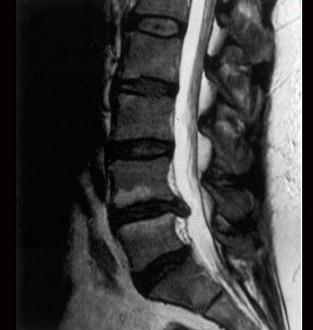

问题 如图所示,对蛛网膜的描述哪项错误 ( )

选项 A、与软膜之间有丝状小梁相连 B、薄而透明 C、为一层韧带 D、与软膜之间为蛛网膜下隙 E、含有网状纤维和弹力纤维

答案 C